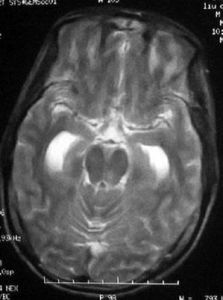

CT掃描可能正常,或顯示腦室縮小,腦溝影消失以及大腦半球凸面有造影劑增強現象。套用釓(gadolinium)增強的MRI能更好地顯示蛛網膜下腔內的炎症。應仔細審視有無腦膿腫,鼻竇炎,乳突炎,顱骨骨折以及各種先天性畸形。在較後時期可發現靜脈性梗塞或交通性腦積水。